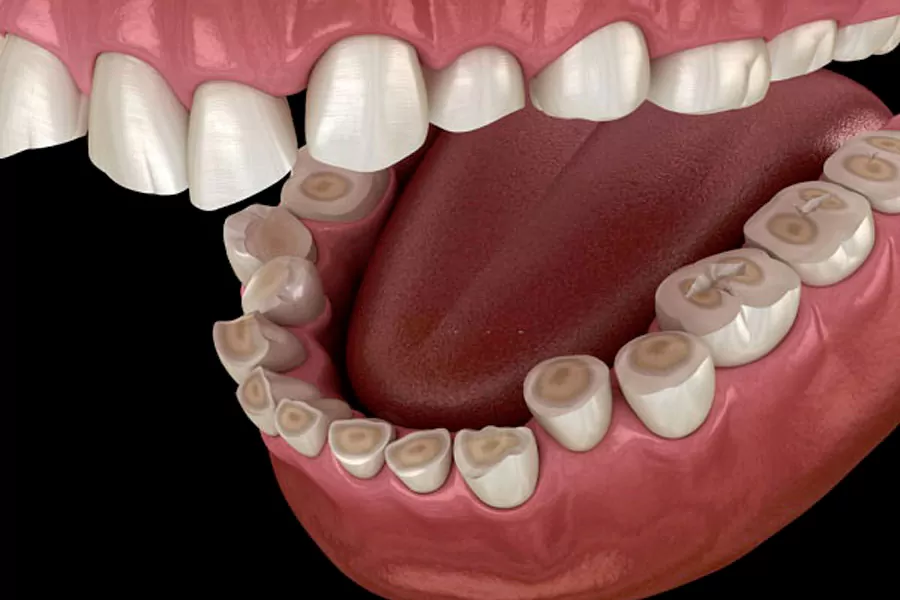

• تآكل أو تشقق في الأسنان

• تآكل الأسنان وقصرها

• تصدّع أو كسر في الأسنان

• انحسار اللثة وفقدان العظم الفكي

• تلف المفصل الفكي الصدغي (TMJ)

• مشاكل جمالية في مظهر الأسنان والابتسامة